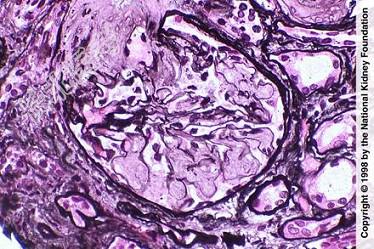

- 单项选择题如图,银染色可见系膜区及毛细血管袢有淀粉样物质沉积, 刚果红染色呈砖红色阳性,电镜以淀粉样纤维沉积为特点, 其病理诊断可考虑为 ( )